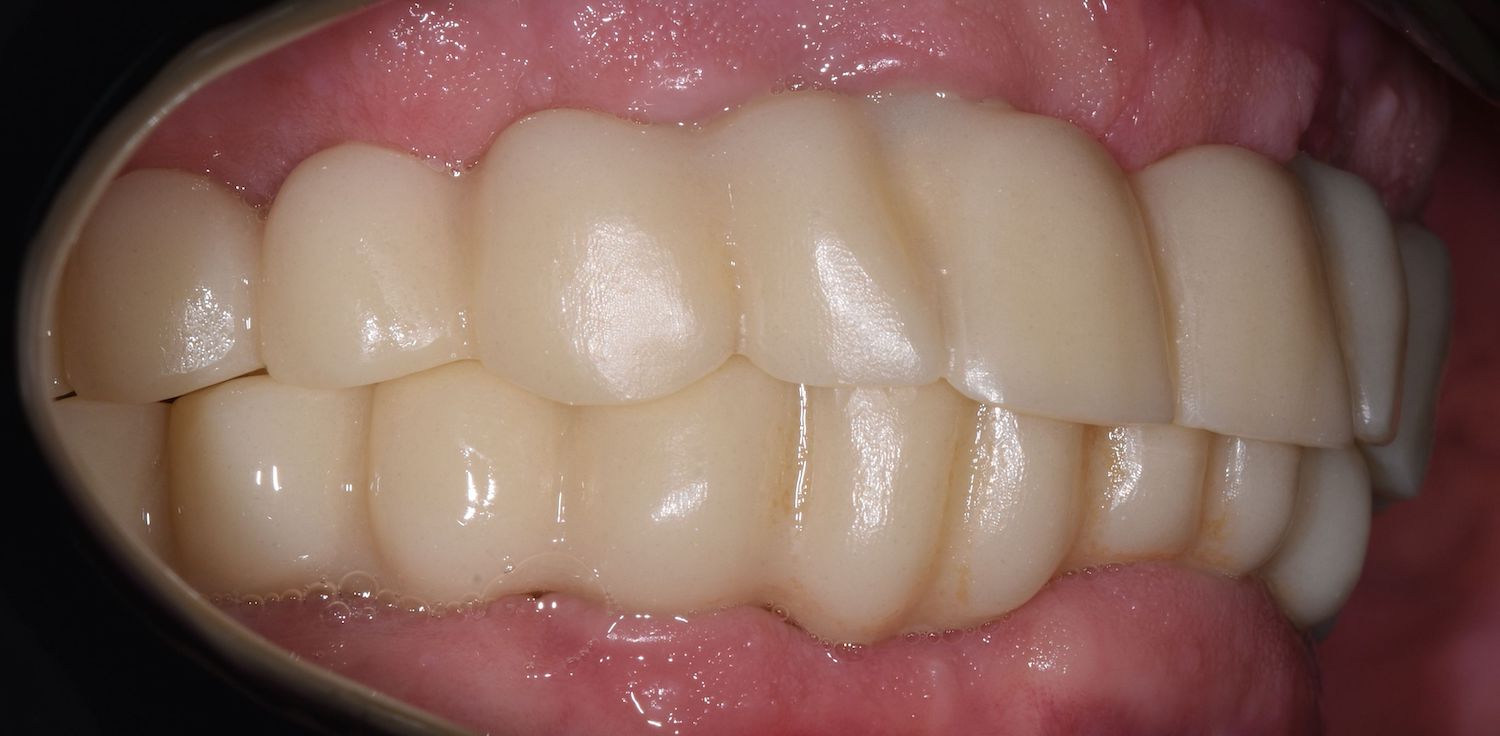

Po odsouhlasení přesného dosedu, správného tvaru a skusu zhotovujeme definitivní zubní náhradu 👇

implantatove-korunky-jslab